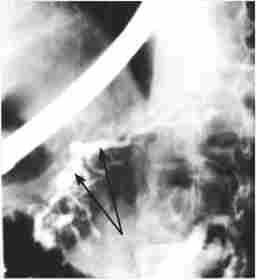

Істотне діагностичне значення має рентгенологічне дослідження шлунка і особливо дванадцятипалої кишки. При рентгенографії шлунка виключаються його органічні ураження, що можуть мати відношення до патогенезу панкреатиту, і іноді виявляються деформації, пов'язані зі змінами в підшлунковій залозі (рис. 20.4), наприклад вдавлення при наявності псевдокист, опухолевидной форми ХП і т. Д.

Деформація контуру вихідного відділу шлунка і розворот дванадцятипалої кишки при кісті головки підшлункової залози

Мал. 20.4. Деформація контуру вихідного відділу шлунка і розворот дванадцятипалої кишки при кісті головки підшлункової залози

Дуоденографія дає можливість судити про вільному пасажі барію через дванадцятипалу кишку або про наявність дуоденостаза, як уже згадувалося, має значення в патогенезі ХП. Інформативним методом виступає рентгенологічне дослідження дванадцятипалої кишки в умовах медикаментозної (штучної) гіпотонії, що досягається попереднім введенням спазмолітиків, наприклад атропіну. До характерними ознаками хронічного панкреатиту, виявлення яких сприяє гіпотонія, відносяться розширення підкови дванадцятипалої кишки внаслідок збільшення розмірів головки ПЖ і наявність на медіальній стінці спадного відділу кишки широкого дефекту наповнення, іноді стенозирующего просвіт і утрудняє пасаж барію (рис. 20.5).

Дуодеіографія з гіпотонією

Мал. 20.5. Дуодеіографія з гіпотонією. На знімку видно розширення підкови дванадцятипалої кишки і здавлення кишки на рівні низхідній і нижньої горизонтальної її гілок збільшеною головкою підшлункової залози